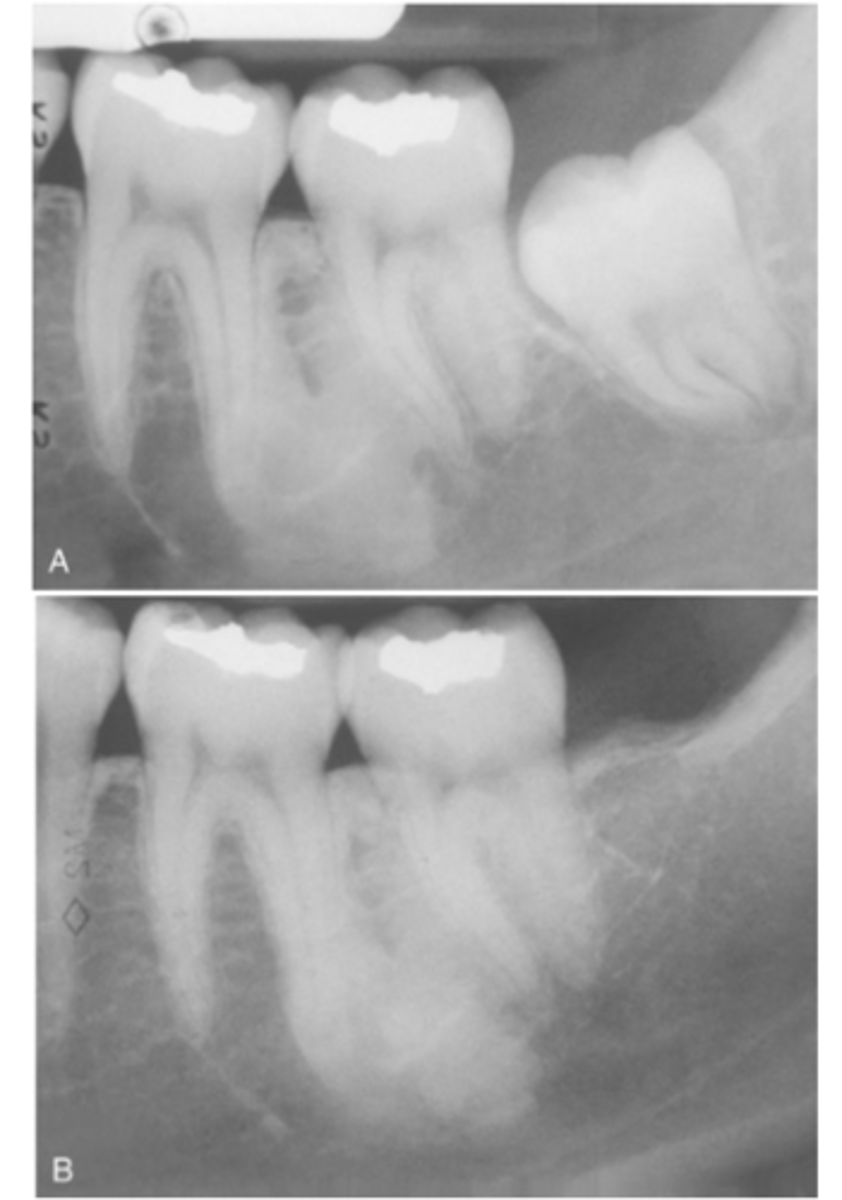

How is Idiopathic Osteosclerosis typically detected?

It is usually found incidentally during routine radiographic examination.

Where are most cases of Idiopathic Osteosclerosis found?

90% of cases affect the mandible

What teeth (in order) in the mandible are most affected in Idiopathic Osteosclerosis

1. First molar area

2. Second molar area

3. Third molar area

What do radiographic signs show in Idiopathic Osteosclerosis

Well-defined radiopacity

Most are associated to a root apex